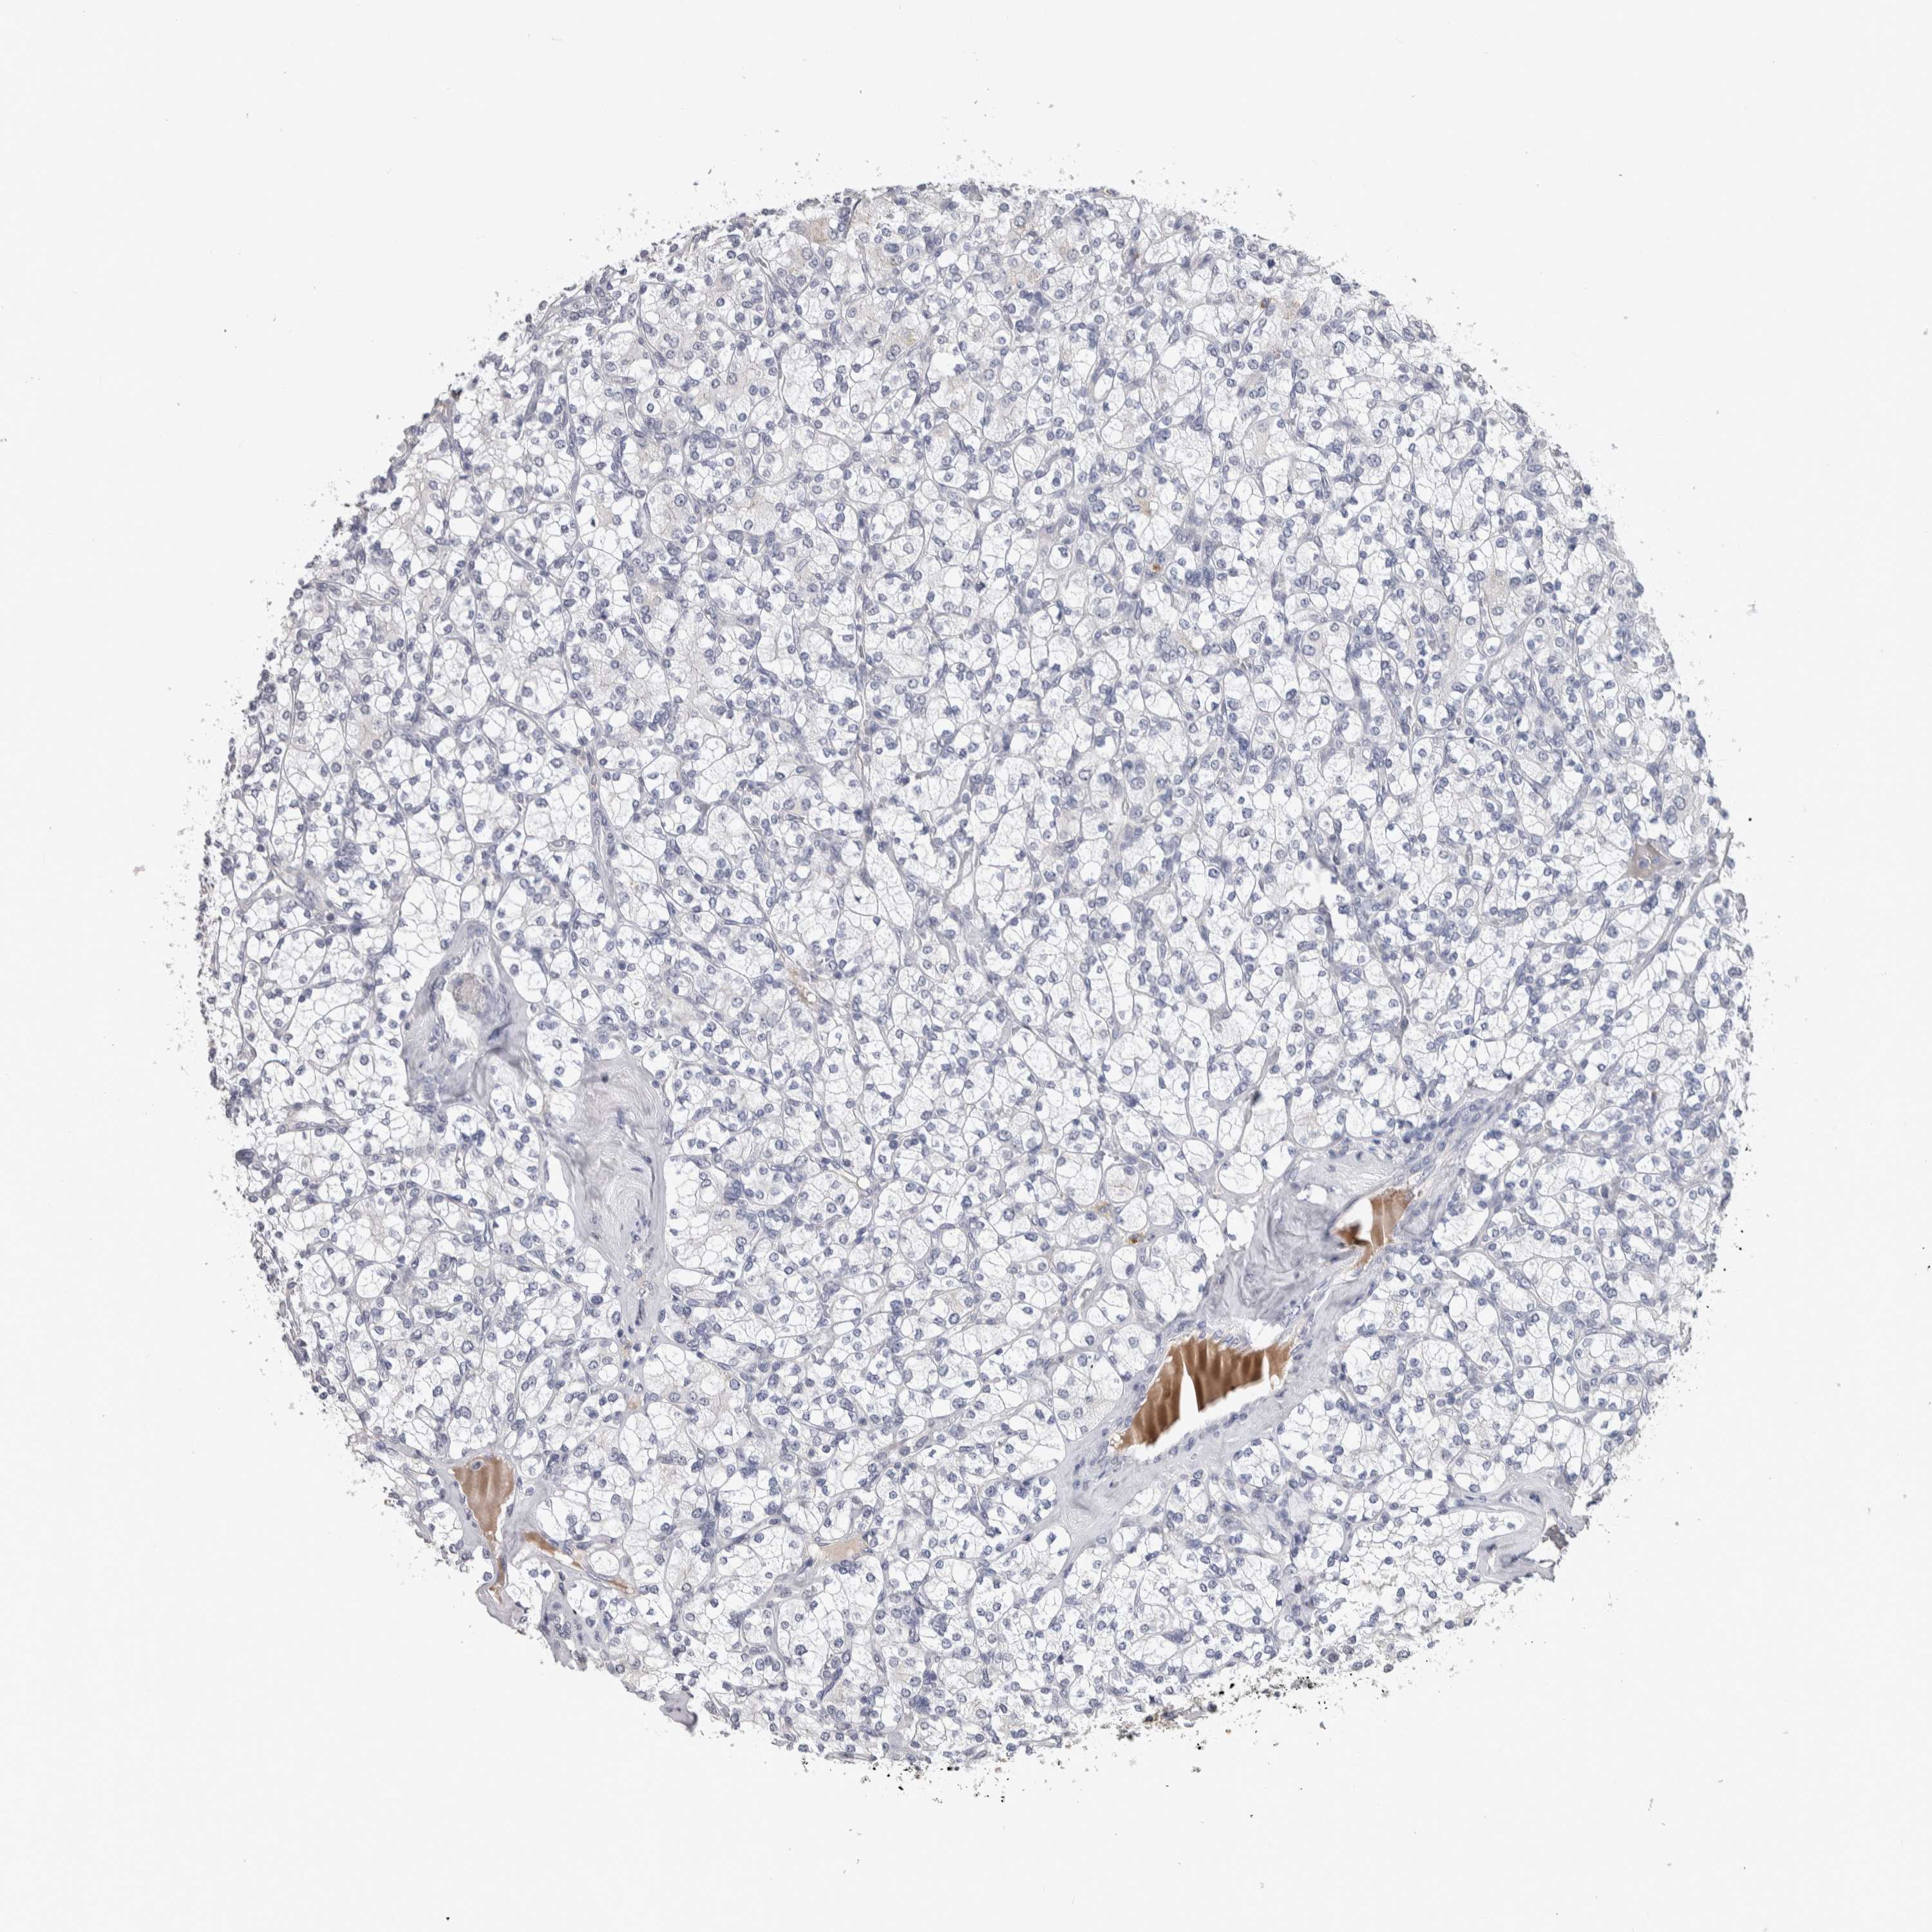

KIDNEY RENAL CLEAR CELL CARCINOMA (TCGA) - Interactive survival scatter ploti

The Survival Scatter plot shows the clinical status (i.e. dead or alive) for all individuals in the patient cohort, based on the same data that underlies the corresponding Kaplan-Meier plots. Patients that are alive at last time for follow-up are shown in blue and patients who have died during the study are shown in red.

The x-axis shows the expression levels (FPKM) of the investigated gene in the tumor tissue at the time of diagnosis. The y-axis shows the follow-up time after diagnosis (years). Both axes are complimented with kernel density curves demonstrating the data density over the axes. The top density plot shows the expression levels (FPKM) distribution among dead (red) and alive patients (blue). The right density plot shows the data density of the survived years of dead patients with high and low expression levels respectively, stratified using the cutoff indicated by the vertical dashed line through the Survival Scatter plot. This cutoff is automatically defined based on the FPKM cutoff that minimizes the p-score. The cutoff can be changed by dragging the vertical line or by entering a cutoff value in the square labeled "Current cut-off".

Under the Survival Scatter plot the p-score landscape (black curve; left axis) is shown together with dead median separation (red curve; right axis). Dead median separation is the difference in median mRNA expression between patients who have died with high and low expression, respectively. It is calculated as follows: median FPKM expression of dead patients with high expression - median FPKM expression of dead patients with low expression. This is intended to aid the user in visually exploring custom cutoffs and the associated p-scores and dead median separation.

Individual patient data is displayed and can be filtered by clicking on one or more of the category buttons on the top of the page. Categories describing expression level and patient information include: high, low, alive, dead, female, male and tumor stages. The scale of the x-axis can be toggled between linear and log-scale by clicking on the "x log" button. Mouse-over function shows TCGA ID, patient information and mRNA expression (FPKM) for each patient.

& Survival analysisi

Kaplan-Meier plots summarize results from analysis of correlation between mRNA expression level and patient survival. Patients were divided based on level of expression into one of the two groups "low" (under cut off) or "high" (over cut off). X-axis shows time for survival (years) and y-axis shows the probability of survival, where 1.0 corresponds to 100 percent.

TMEM102 is potential prognostic, high expression is favorable in Kidney Renal Clear Cell Carcinoma (TCGA)

: 2.51

Average pTPM 3.5

Number of samples 521